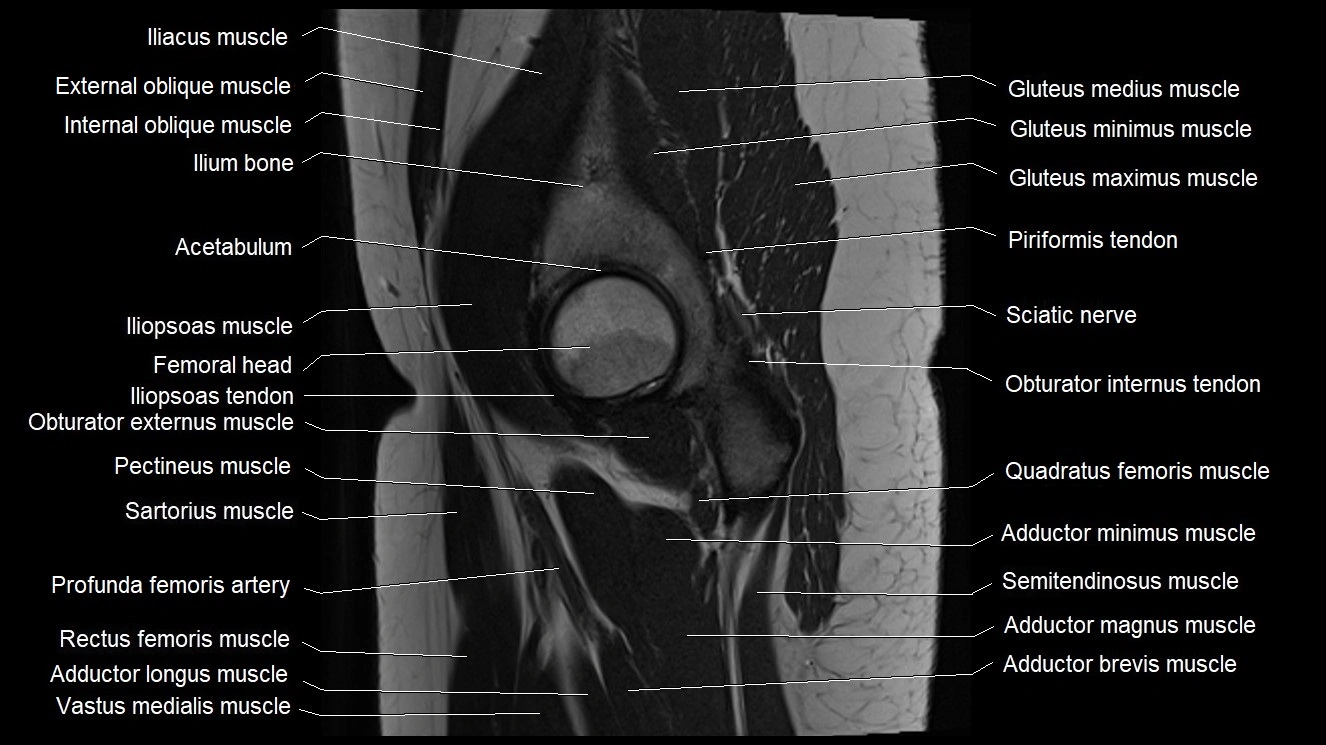

- Acetabulum

- Gluteus medius muscle

- Gluteus minimus muscle

- Gluteus minimus tendon

- Head of femur

- Iliopsoas muscle

- Iliopsoas tendon

- Inferior gemellus muscle

- Obturator externus muscle

- Obturator internus tendon

- Pectineus muscle

- Quadratus femoris muscle

- Rectus femoris muscle

- Sartorius muscle

- Vastus medialis muscle